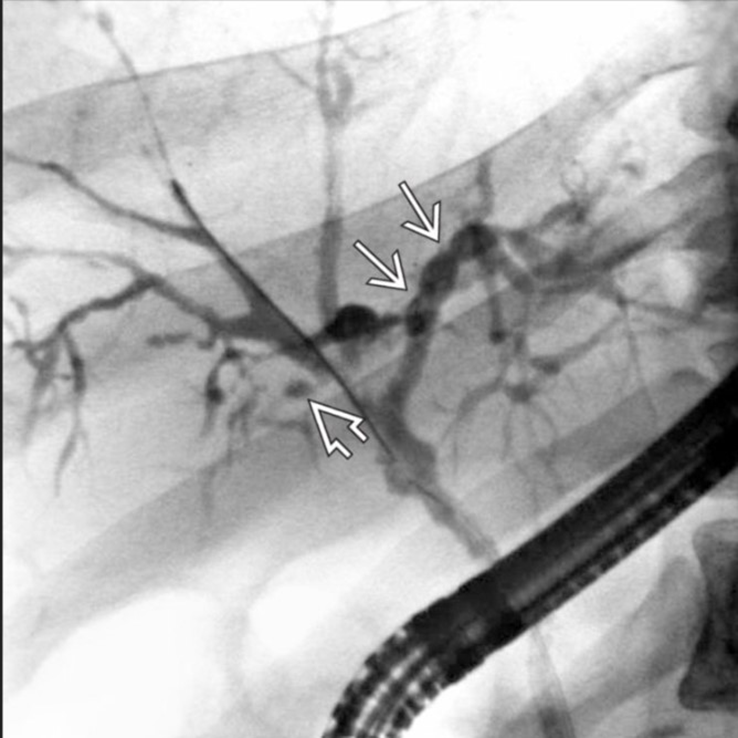

PSC diagnosis

endoscopic retrograde cholangiopancreatiography or MRCP

progressive inflammatory fibrosis and destruction of intra and extra hepatic bile ducts

cholestatic liver profile

cholangiography

pANCA 65-80%

liver biopsy rarely diagnostic - 10% onion skin

PSC